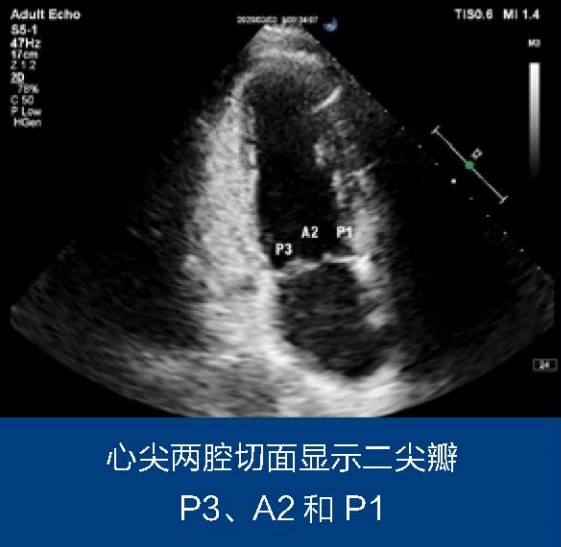

根据当前的权威指南推荐,2D/3DEcho-assessment forMitralValveRepair可以精准地分析二尖瓣瓣膜的病变情况,明确有效反流面积等关键信息,有助于术者实现高效的外科处理,减少安全事件的发生。AlainBerrebi教授结合实际超声成像及其临床实践经验,详细解说了2D/3D超声心动图在二尖瓣修复手术中的指导作用和应用策略。他强调了精准性、有效性和共同语言的必要性,以便心脏外科术者与超声科医师在术中能够密切交流。基于不同的超声心动图切面,可以进行系统性的全心动周期瓣膜评估,并重点观察是否存在功能不全、病变、病因学、二尖瓣收缩期前向运动(SAM)风险以及同期三尖瓣的情况,进而指导手术策略的制定,为患者提供个体化手术处理。

其中,郭惠明教授团队展示了一例50岁男性的病例。经TTE评估,该患者被诊断为二尖瓣P3脱垂,反流束面积为14.0cm05,重度二尖瓣关闭不全伴瓣叶脱垂。术中,通过TEE进一步明确了二尖瓣反流和解剖情况。结果显示,前叶A2区瓣体长达35mm,属于严重Barlow综合征早期。